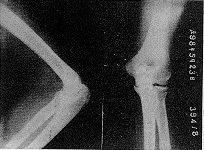

儿童到成人的整个骨发育过程中,无论从外观形态还是X线影像上观察,肱骨下端的变化都是很明显的。从肱骨下端各二次骨化中心依次出现到骨骺行将闭合、骨形态成熟接近成人,一般要到14~17岁才能完成。在儿童期,无论X线影像还是骨标本实际测量(笔者曾进行过骨标本实际测量),其骺软骨以上的骨干部基本没有前倾角,少量的下端外形前倾角是骺软骨二次骨化中心偏前形成的干骺角所致。前倾角是骨发育过程中逐步形成和完善的。以7岁儿童为例,我们实测干骺角为6°~8°,而成人则在30°~50°[3](见图1)。4、9岁及成人肱骨下端X线片前倾角变化(见图2~4)。

图4 成人肱骨下端X线片

Fig 4 X-ray film of an adult's humerus